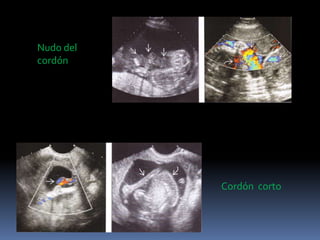

Nudo del

cordón

Cordón corto